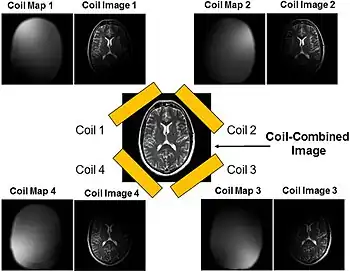

Parallel imaging coil collection

Parallel imaging involves the addition of multiple coils surrounding the target with each coil acquiring a fraction of the total image. Because modern GPUs have parallel processing capabilities, they can reconstruct each portion of the image simultaneously. Therefore, the more coils used, the faster the acquisition of the MR images.[15]